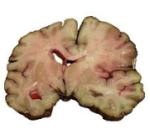

На серии мскт определяется справа в лобно-теменной области гиподенсивный участок плотностью 14ед.Х., размерами 59*36*55мм. Дифференцировка серого и белого вещества правой гемисферы не четкая. Срединные структуры мозга не смещены. Кальциноз стенок интракраниального сегмента позвоночных артерий, ВСА, базилярной, мозжечковых артерий. Последствия перенесенного двухстороннего гайморита, этмоидита. Остеохондроз С3-4, С4-5, С5-6 дисков ШОП

Желудочковая система, базальные цистерны мозга, наружные ликворные пространства умеренно расширены. Ширина передних рогов боковых желудочков справа 7,6 мм, слева 9,7мм: ширина III желудочка 8,6 мм (норма до 60 лет <7мм, старше 60лет < 9мм). Параселлярные, ретробульбарные структуры без особенностей.

Деструктивных изменений со стороны костей мозгового черепа не наблюдается. Пневматизация ячеек височных костей не нарушена. В верхнечелюстных пазухах пристеночные образования, до 7мм, частично затемнены ячейки решетчатой кости.

Заключение:

кт-признаки ОНМК по ишемическому типу справа в лобно-теменной области на фоне сосудистой энцефалопатии. Кальциноз стенок интракраниального сегмента позвоночных артерий, ВСА, Базилярной, мозжечковых артерий.